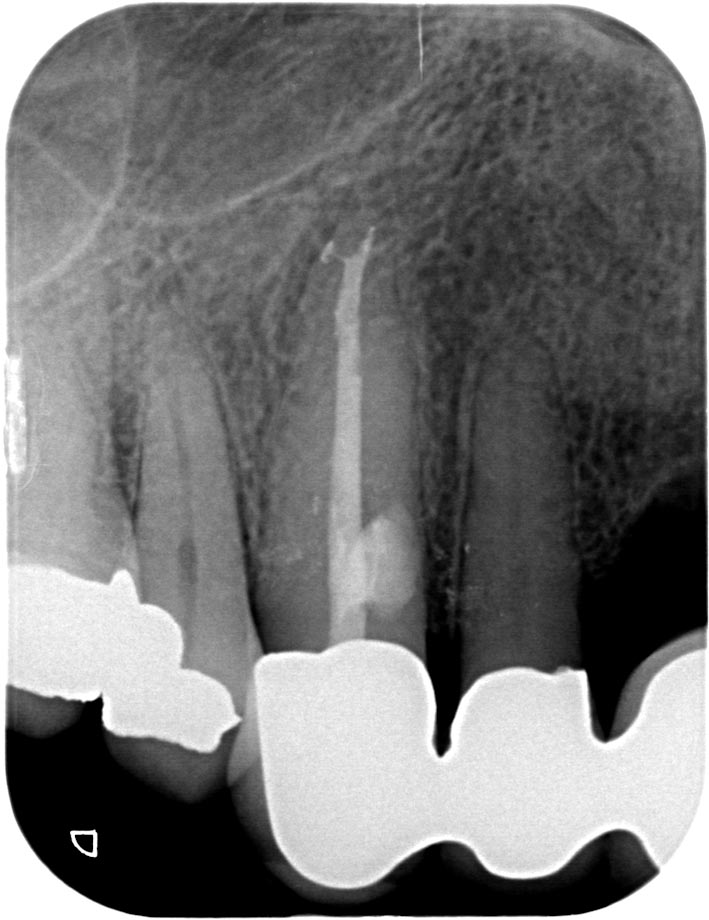

ER-3 Veröffentlicht 17. Juni 2013 am 709 × 920 in Was zeigt das DVT (4) – Resorptionen – Die Antworten – Fall 1